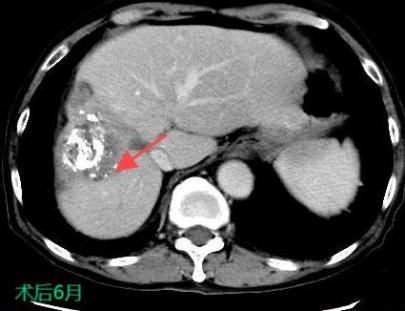

三、肝癌的介入治療

TACE/HAIC:經肝動脈灌注化療栓塞(TACE)、肝動脈內灌注化療藥物(HAIC)是在不開刀暴露腫瘤病灶的情況下,在皮膚上做直徑幾毫米的切口,在影像設備的引導下,導絲和導管插入肝臟腫瘤供血管,注入栓塞劑和化療藥物,使肝臟腫瘤內化療藥物濃度提高,并減少全身的藥物總濃度,達到提高化療效果并減少毒副作用的目的。對于無法手術切除的巨塊型肝癌、肝內多發肝癌病灶、肝癌結節破裂出血有良好的治療效果。

肝癌的介入治療

射頻熱消融:被廣泛地用于原發性肝癌的治療,將電極針插入腫瘤通過射頻能量使病灶局部組織產生高溫,凝固腫瘤,近似于外科手術根治性切除的效果。

射頻熱消融治療